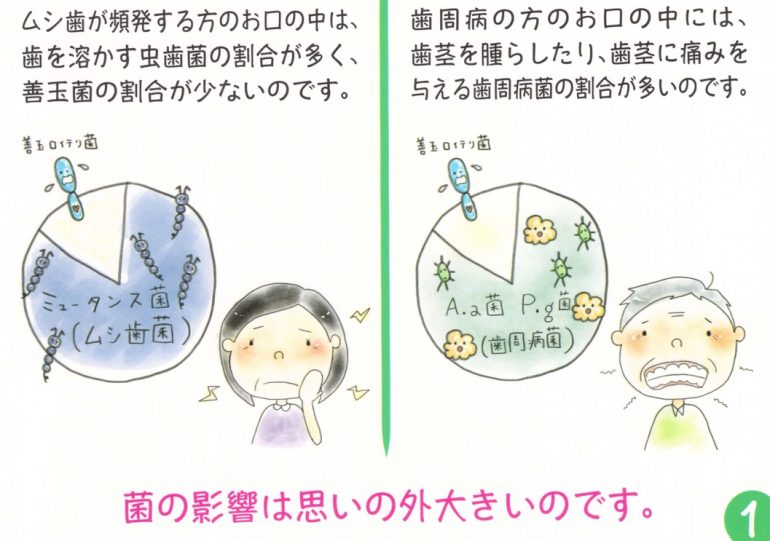

市販の歯磨き粉には薬品の成分ですっきり感じるようにしたり、歯磨剤が入り歯の表面を細かく傷が入り磨いているのにプラークや細菌が歯の表面に付着しやすくなります。磨いているのに、虫歯になってしまうのは歯の表面に付着する虫歯菌が取れていないためです。

薬品成分の殺菌剤が含まれている歯磨き粉で磨くとお口の中の善玉菌も殺菌されるため、善玉菌と悪玉菌のバランスが崩れ、逆に悪玉菌が活発に活動してしまうことも・・・

※歯に影響する悪玉菌とは虫歯菌と歯周病菌のことです

口腔内環境は常に正常な状態に保ち、善玉菌が優位な状況を作ることが大切です